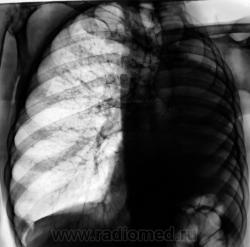

Пациент, заслуженный в прошлом, подданный "Его Величества", 10 лет тому был прооперирован - левосторонняя пульмонэктомия по поводу фиброзно-кавернозного туберкулёза. Вроде-бы все было нормально, время - от времени шел на встречу к работникам фтизиатрической службы, являясь после неоднократных напоминаний, делая им одолжение... Но в последние 3 года пропал. 2 месяца тому был найден, приглашен и явился. Чувствовал себя хорошо, даже не стал возражать против рентгенографии. Но смутили очаги, которых ранее не было в верхней доле правого лёгкого.

Повторили и "прямую", и произвели томограммы.

Очаговый туберкулез верхней доли?

туберкулёз правого лёгкого.

Мы тоже склонились в пользу диссеминированного.

Важно то, что мы "посылальщика" упаковали. Выставлен диссеминированный туберкулёз.